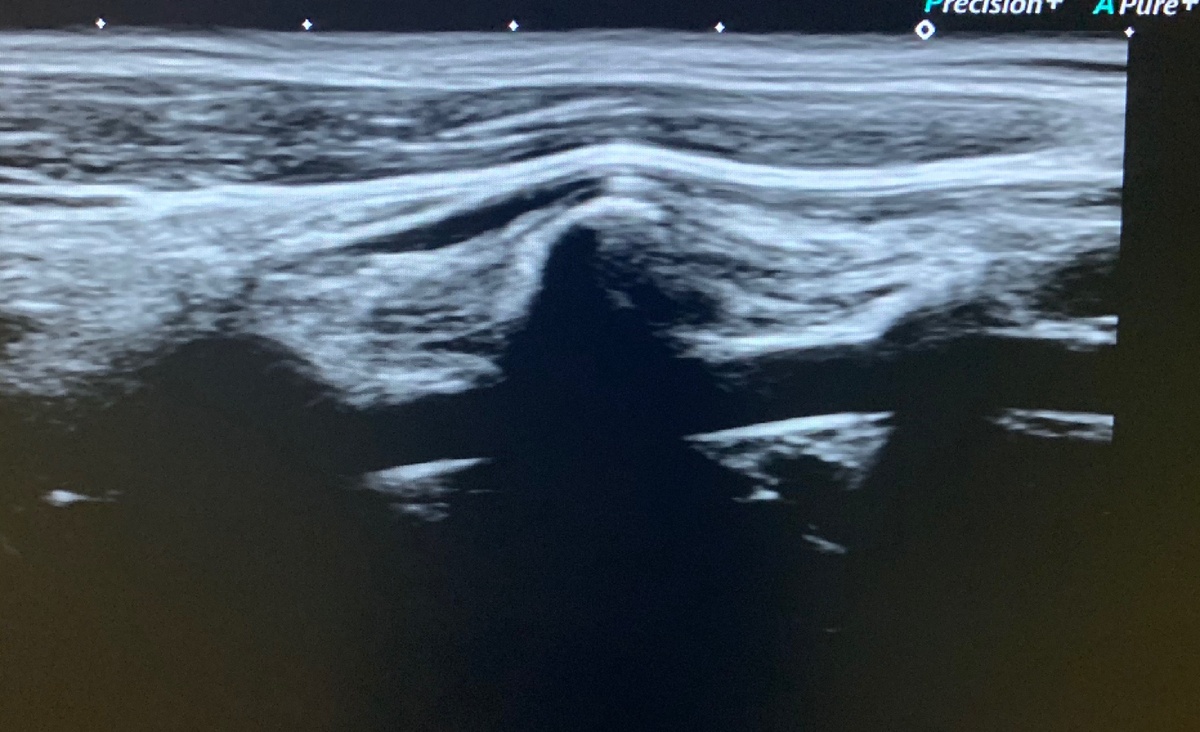

Одним из часто назначаемых неврологом исследований является ультразвуковая доплерография/УЗИ сосудов шеи. Синонимом является УЗДГ брахиоцефальных артерий.

Нормальные показатели кровотока в позвоночной артерии